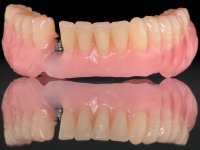

Two dental implants were planned in the CBCT scan, in the area of the inferior canines. The dental extractions were performed and, simultaneously, the alveolar crest was flattened and the implants were placed. Three issues were considered while implant placement: parallelism of the axis, same height of the implant’s neck, and same position in the coronal plan. This 3D insertion is essential to have a good retention of the overdenture in the future. Patient’s removable denture was fixed in the dental lab, to include the extracted teeth, and a soft-tissue relining was done over the healing abutments. After the osseo-integration period, a first impression was done with an open-tray and a doble-mix technique. This dental impression allowed the production of screwed wax-rims and an individual tray for a functional impression. A second impression, final, was done with an individual tray with a monophasic silicone. The occlusal wax-rims were correct in the mouth according to the full denture guidelines. Special care was taken with the occlusal vertical dimension and the support in the soft-tissues. A silicone bite registration material was used to better defined the intermaxillary relations. Teeth set-up was done in the dental lab with the selected tooth color. Due to the fact that the base was screwed to the dental implants, the teeth set-up was functionally evaluated in the mouth. Another silicone bite registration material was used to allow final occlusal adjustments. Finally, the locators were screwed and the retention nylons were selected according to the patient needs.